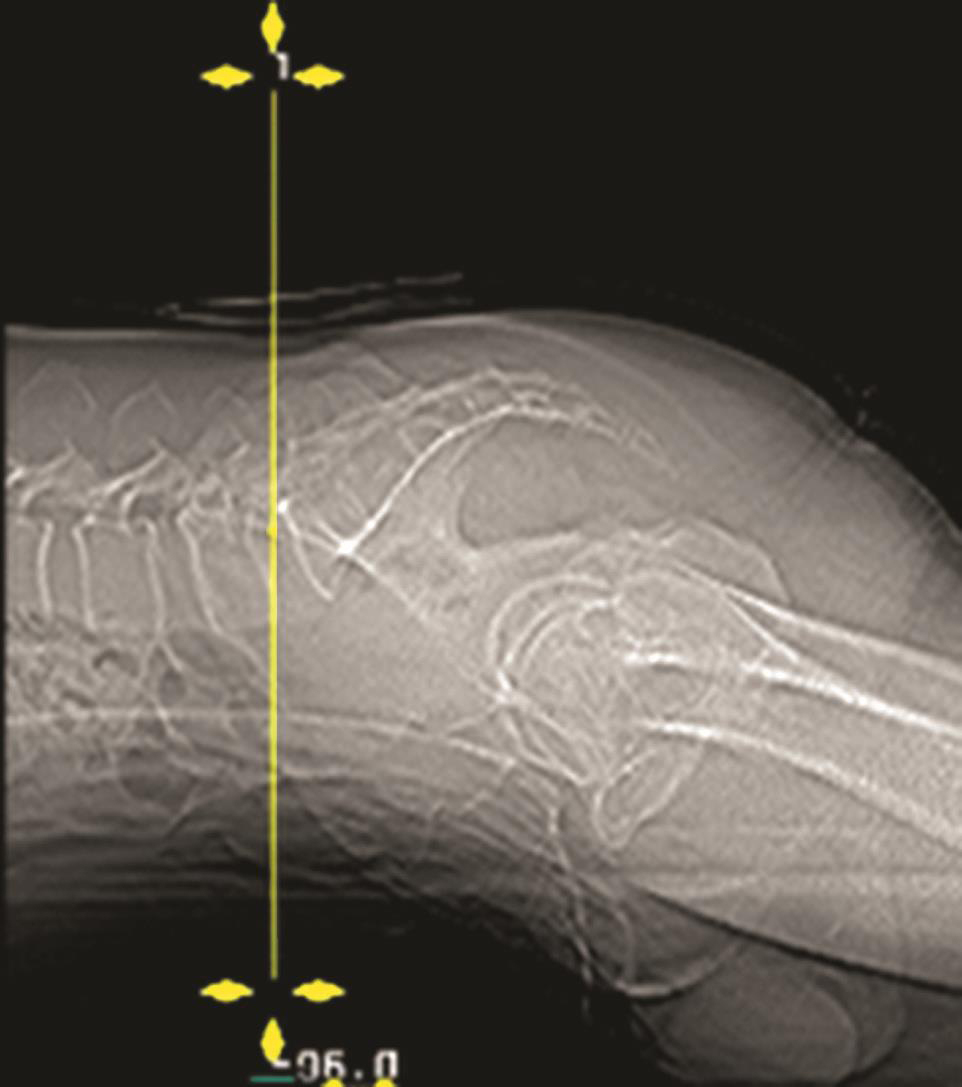

无论什么手术都必须做TOP像扫描,在其上确定手术部位和断层扫描范围。如侧卧位时的椎间隙侧方穿刺入路做脊柱的正位TOP像(图3-3-6),俯卧位时的椎板间入路做脊柱的侧位TOP像(图3-3-7)。

图3-3-6 侧卧位的正位TOP像

A.无髂骨阻挡时机架零度扫描;B.有髂骨阻挡时的角度扫描

一般的CT机架可以调整角度(图3-3-8),调整机架角度进行扫描是寻找操作平面的关键举措,不同的穿刺途径和手术目的要求机架调整的角度也不同,如L 4/5 经椎间隙侧方入路时,如果手术平面无髂骨阻挡,则采用零度扫描(见图3-3-6A、图3-3-8B),否则为了避开髂骨阻挡,机架应向头侧倾斜(图3-3-6B、图3-3-8C);用于射频靶点消融或内镜髓核摘除的椎板间入路,如果扫描角度与椎间隙平行,将多有椎板阻挡(图3-3-9),其要点在于穿刺靶点为直接突出的椎间盘,而穿刺途径又必须避开椎板经过椎板间隙才能成功,因此要求调整到既能显示靶点又经过椎板间隙的角度,一般向足侧倾斜(图3-3-8A、图3-3-10);椎弓根入路则沿椎弓根轴线扫描(图3-3-11)。